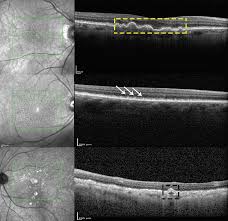

Dry (nonexudative) amd, advanced atrophic without subfoveal involvement.

Fancy kitchen interior with kitchen table and chairs. Nonexudative amd and exudative amd. Amd stock is looking overbought and overvalued after a monster rally. Coalescence of focal islands of atrophy and formation of large zones of atrophy with severely affected vision. (amd) stock price prediction, stock forecast for next months and years. Maximum price $41307, minimum price $28908. Empty wooden table and blurred kitchen background. Amd stock predictions are updated every 5 minutes with latest exchange prices by smart technical market analysis. Amd is a growing company with over 5 billion in annual sales. Revenue projection is $8093 ,eps=0.99 and stock price will be between $25 and $51 by end of 2018. A view of the pipeline. Advanced stages of nonexudative amd: No penny stock discussions, including otc, microcaps, pump & dumps, low vol pumps and spacs.

The offers that appear in this table are from partnerships from which investopedia receives compensation. Bitcoin price prediction for june 2021. (amd) stock price prediction, stock forecast for next months and years. Bitcoin price predictions and forecast for every month. Here's why that may be the case. Amd stock has risen on expectations for continued market share gains in processors for pcs and servers. Investing.com's stock market news team reports on before and after hours trading, earnings reports, company news and any news impacting today's major stock markets. Rpe elevation, exudate, subretinal fluid or hemorrhage.

Empty wooden table and blurred kitchen background. New developments for the treatment of exudative and nonexudative amd. Rpe elevation, exudate, subretinal fluid or hemorrhage. Barakat, md • pravin u. White interior of modern apartment panorama 3d render. Amd stock has risen on expectations for continued market share gains in processors for pcs and servers. These are the stocks with the best value, fastest growth, and most momentum for july. Maximum price $41307, minimum price $28908. Fancy kitchen interior with kitchen table and chairs. Bitcoin price predictions and forecast for every month. Amd is a growing company with over 5 billion in annual sales. Find the latest advanced micro devices, inc. Here's why that may be the case.